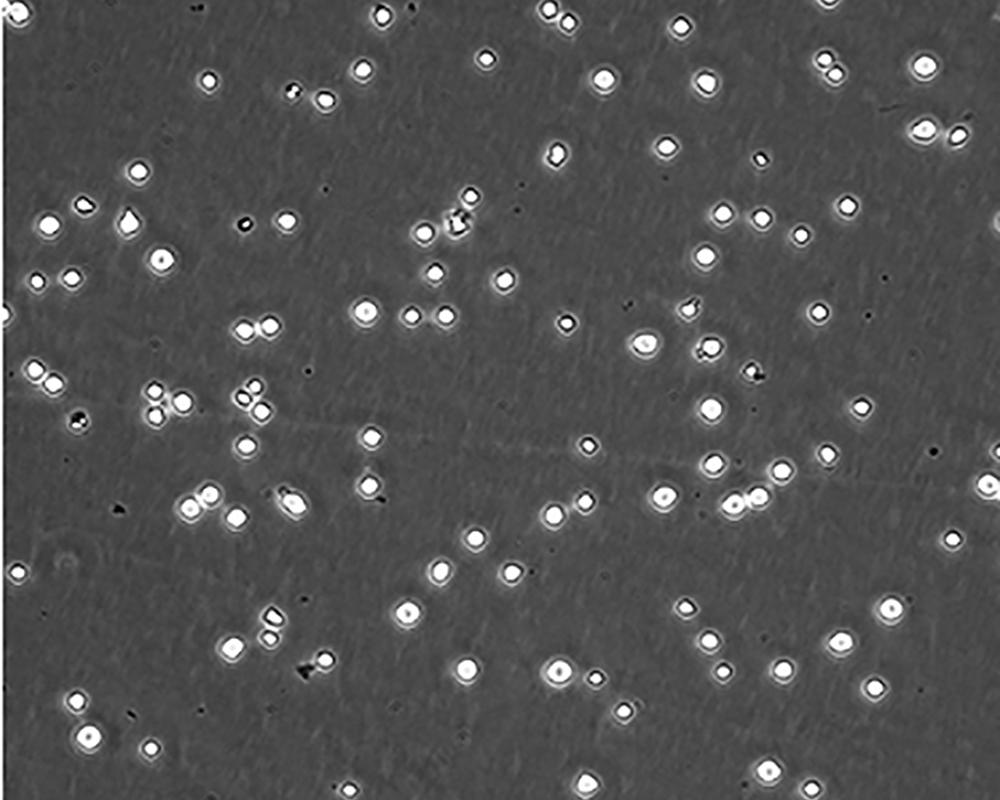

中文名稱 人急性淋巴細胞白血病細胞

組織來源 急性T淋巴細胞白血病;女性

生長特性 suspension

形態特征 lymphoblast

細胞描述 CEM/C1是人T細胞白血病細胞株CCRF-CEM(見ATCC CCL-119)具有喜樹堿抗性的衍生株。1991年細胞株選擇并亞克隆了對CPT的抗性。細胞表現出對CPT類似物水溶性的托泊替康和非水溶性的9-氨基-CPT及10,11-亞甲二氧基-CPT具有交叉抗性。CEM/C1細胞對CPT的敏感性較母系CEM細胞低31倍。CEM/C1細胞表現非典型的多藥抗性和轉換拓補異構酶I催化活性。對CPT的抗性維持6個月以上。